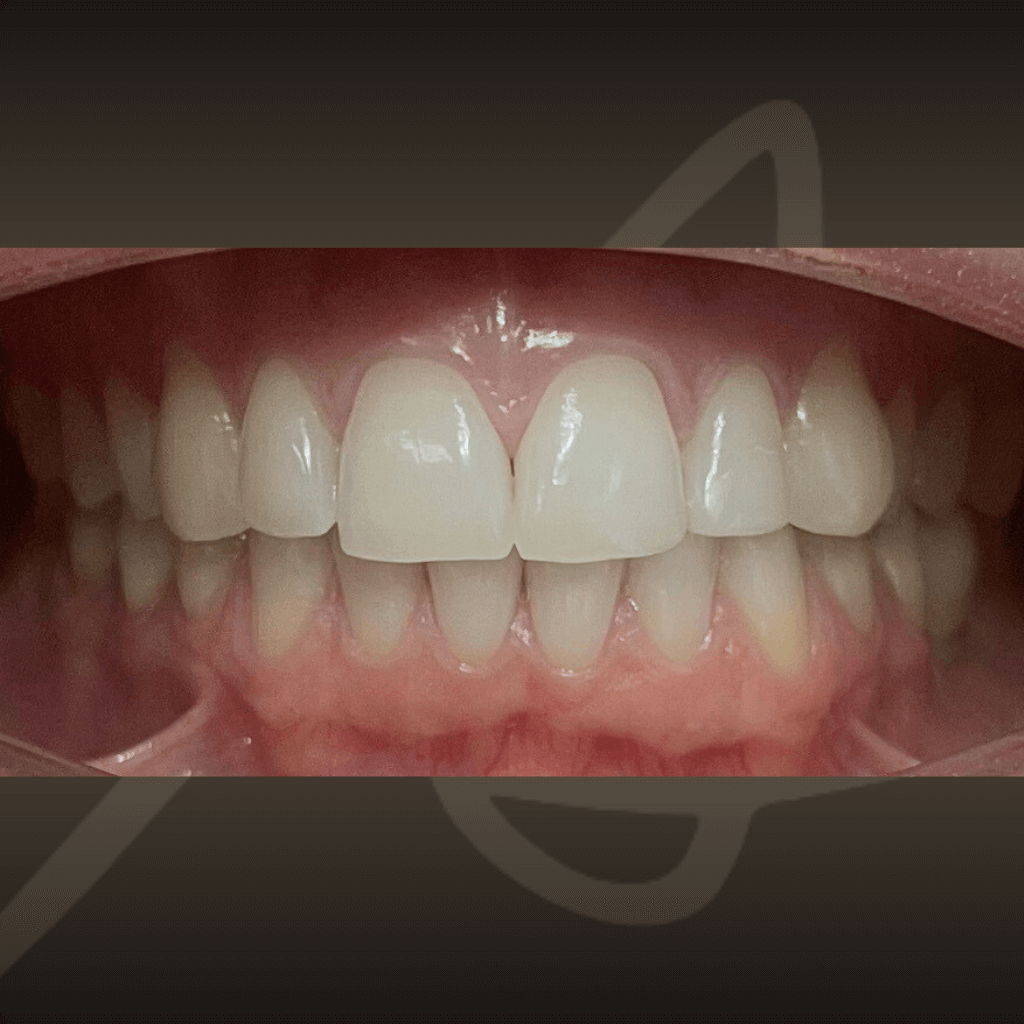

Ортодонтията не е само въпрос на подредба. Правилното лечение подобрява захапката, речта и създава стабилна основа за дългосрочно дентално здраве. Независимо от възрастта, ортодонтското лечение може да допринесе за по-добър функционален баланс и по-лесна поддръжка на зъбите във времето.